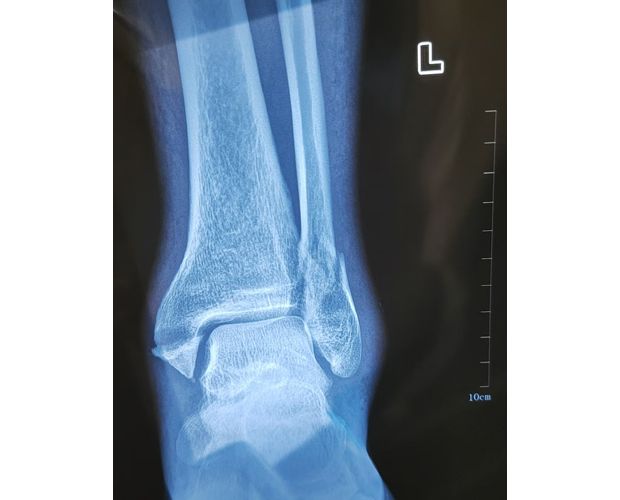

2月4日,何店鎮(zhèn)中心衛(wèi)生院接診一名左踝關(guān)節(jié)外傷患者,經(jīng)影像檢查,確診為左脛、腓骨下段骨折。外科醫(yī)生姜穩(wěn)迅速完成術(shù)前檢查及病情評估,并與患者及家屬深入溝通治療方案。在患者強烈要求于本院進行手術(shù)的情況下,為最大限度保障手術(shù)質(zhì)量與安全,該院特邀請醫(yī)共體牽頭單位——曾都區(qū)人民醫(yī)院脊柱創(chuàng)傷外科專家團隊前來指導(dǎo)。

本次幫扶由曾都區(qū)人民醫(yī)院脊柱創(chuàng)傷神經(jīng)外科主任徐三軍帶隊,專家團隊抵達后立即完成手術(shù)風險評估及術(shù)前準備。手術(shù)過程中,徐三軍主任嚴格規(guī)范完成各項手術(shù)操作,并同步結(jié)合手術(shù)步驟,為該院外科醫(yī)師詳細講解骨折手術(shù)的關(guān)鍵要點、操作技巧、術(shù)中注意事項及術(shù)后康復(fù)要領(lǐng)。通過“手把手”的實戰(zhàn)帶教,專家將豐富的手術(shù)經(jīng)驗與規(guī)范的診療思路傾囊相授,讓該院醫(yī)護人員在實操中學(xué)習(xí),在過程中成長。